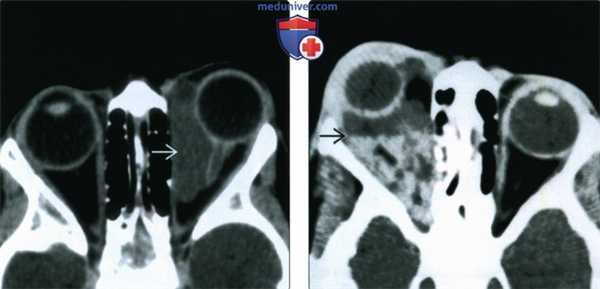

(Слева) При КТ с КУ в аксиальной проекции в медиальной части левой глазницы определяется кистозное четко отграниченное неконтрастируемое образование, стенка образования неразличима. Хотя наблюдается картина простого однокамерного образования, оно лежит в нескольких смежных пространствах, имеет пресептальный компонент и компоненты внутри и вне мышечного конуса.

(Справа) При КТ без КУ в аксиальной проекции у четырехлетнего ребенка определяется неправильной формы многокамерная лимфатическая мальформация глазницы, распространяющаяся в несколько смежных пространств. Расслоение жидкостей с различными плотностями обусловлено оседанием продуктов распада крови, скопившихся при спонтанном кровоизлиянии.

(Слева) При Т2-взвешенной МРТ в аксиальной проекции определяется массивная лимфатическая мальформация сложной формы, вызывающая экзофтальм. Жидкое содержимое, скопившееся в результате неоднократных кровоизлияний, дает вариабельный сигнал и формирует уровни раздела. Также виден еще один, пресептальный, компонент образования.

(Справа) При МРТ Т1ВИ FS с КУ в левой глазнице определяется крупное образование сложной формы, содержащее по большей части неконтрастируемый субстрат, дающий вариабельный Т1-сигнал. Контрастируемая структура с медиальной стороны представляет собой венозный компонента, вероятно, мелкий варикозный узел.